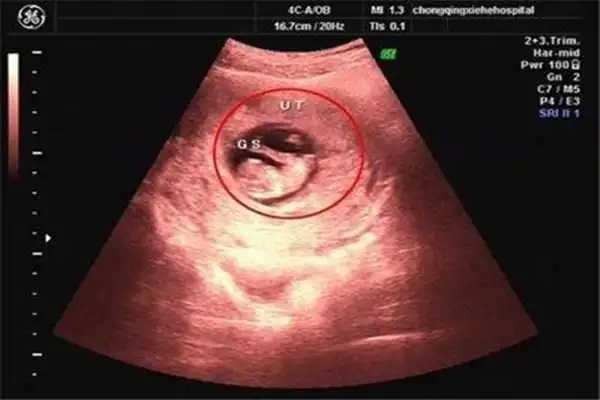

我的孕囊是长条形状还是圆形的?孕囊大小1.37*1.40*0.79cm.

六周的孕囊能看出怀几个孩子吗孕早期通过孕囊形状看男女不靠谱